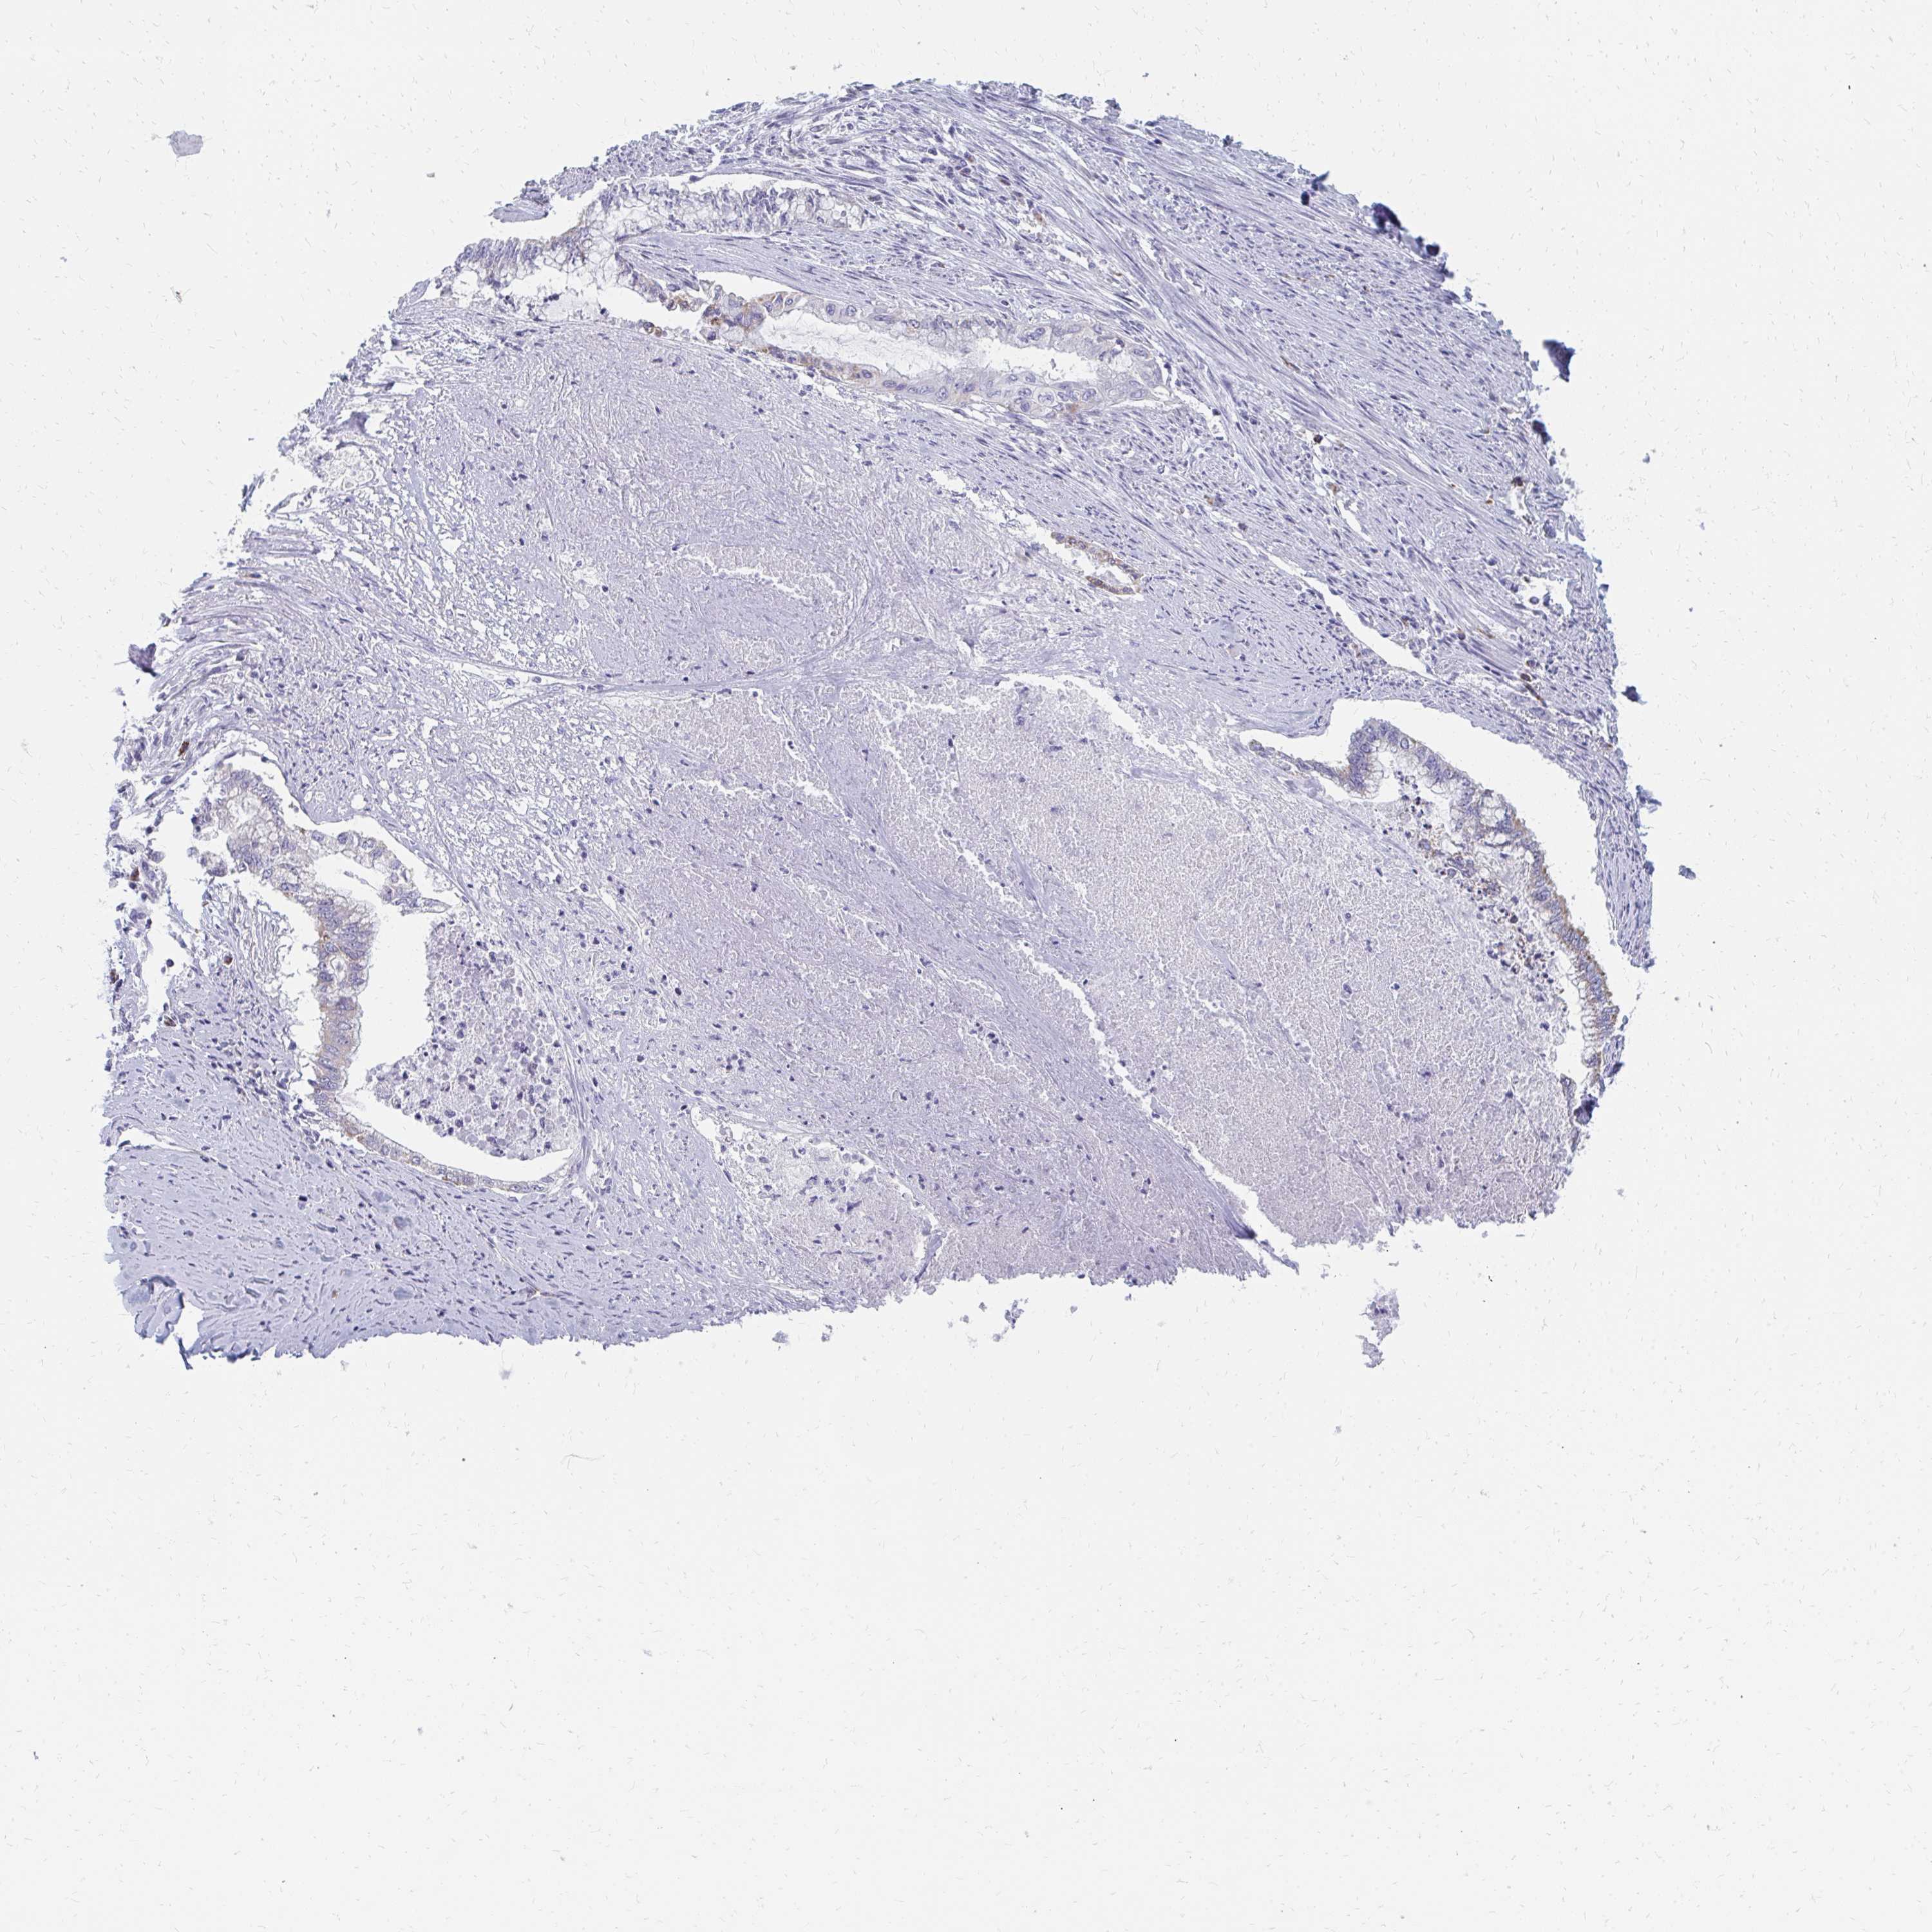

ENDOMETRIAL CANCER - Protein expressioni

A mouse-over function shows sample information and annotation data. Click on an image to view it in a full screen mode. Samples can be filtered based on level of antibody staining by selecting one or several of the following categories: high, medium, low and not detected. The assay and annotation is described here.

Note that samples used for immunohistochemistry by the Human Protein Atlas do not correspond to samples in the TCGA dataset.

Antibody stainingi

Antibody staining in the annotated cell types in the current human tissue is reported as not detected, low, medium, or high, based on conventional immunohistochemistry profiling in selected tissues. This score is based on the combination of the staining intensity and fraction of stained cells.

Each image is clickable and will lead to virtual microscopy that enables deeper exploration of all samples and also displays staining intensity scores, fraction scores and subcellular localization as well as patient and tissue information for each sample.

Antibody HPA060076

Staining

High

Medium

Low

Not detected

Intensity

Strong

Moderate

Weak

Negative

Quantity

>75%

75%-25%

<25%

None

Location

Nuclear

Cytoplasmic/membranous

Cytoplasmic/membranous,nuclear

Adenocarcinoma, NOS